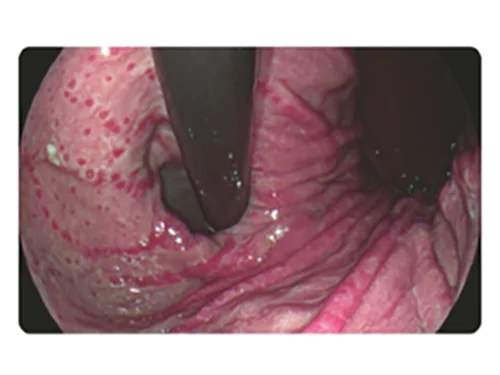

HEI: Улучшенная визуализация гемоглобина

Сочетание узкополосного красного, зеленого и желтого цветов улучшает видимость глубоких кровеносных сосудов и точек кровотечения за счет использования алгоритма слияния изображений и технологии автоматической обработки.

Применение

- Выявление кровотечений (упрощает остановку интраоперационных кровотечений)

- Визуализация варикозно расширенных вен для проведения лечения (упрощает обнаружение целевых вен при инъекционном лечении или перевязке вен).

Белый свет

HEI